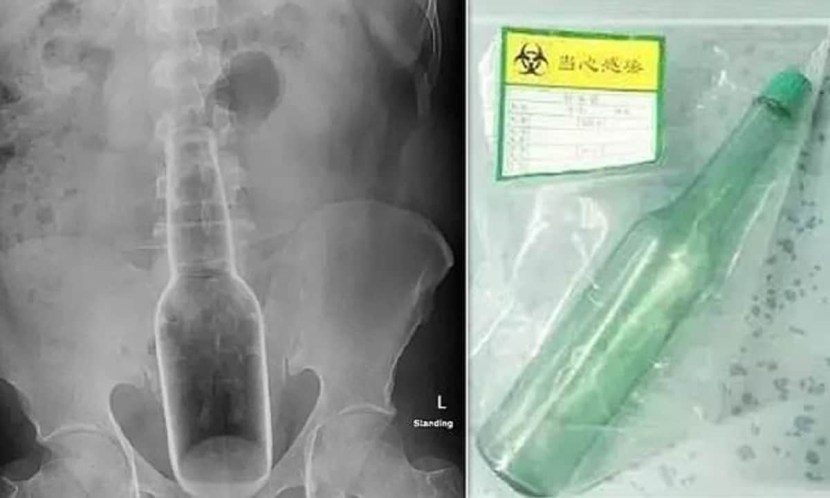

X -ray bottle in the rectum